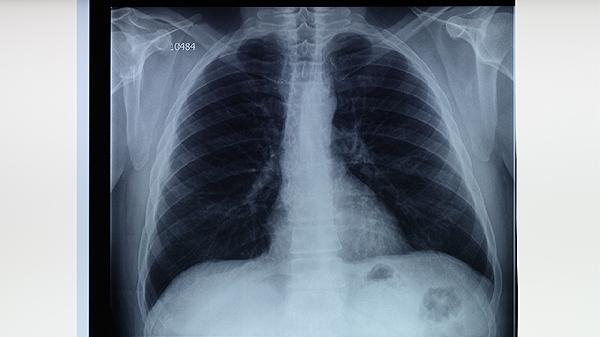

肺结核病的症状主要有咳嗽、咳痰、发热、盗汗等。肺结核病是由结核分枝杆菌感染引起的慢性传染病,症状发展通常从早期表...

婴幼儿结核病可通过结核菌素试验、胸部X线检查、痰涂片镜检、γ-干扰素释放试验等方式检查。 1、结核菌素试验: 通...